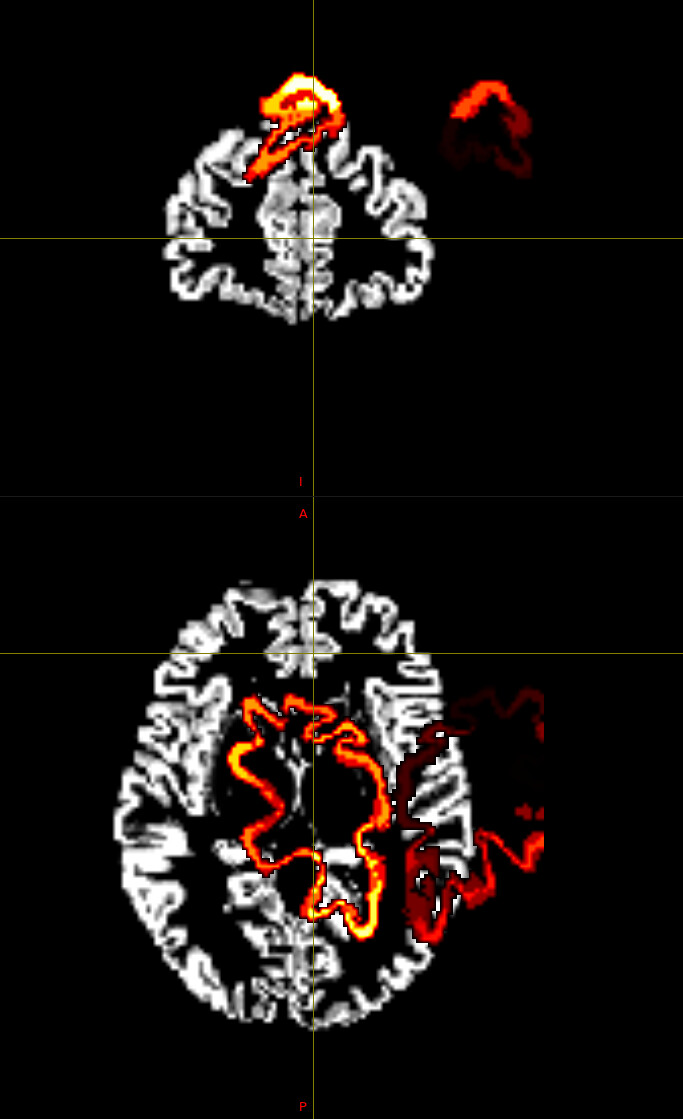

Despite extensive tuning, the final transformed atlas (DKT308_parc.mif) consistently exhibits significant bleeding (invasion) into the white matter (WM) in high-curvature sulcal regions.

I diagnosed this as over-regularization in the FNIRT process (the algorithm prioritizes smoothness over anatomical accuracy).

Visual Evidence

(Please insert the image showing the atlas bleeding into the white matter here)